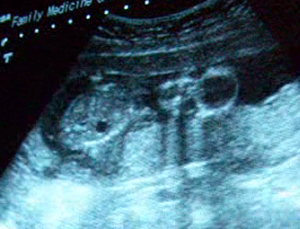

Sono Pic:

18 weeks

October 1st: I didn’t gain weight in the two weeks since my last appointment, maybe just an ounce or two, which is great. I was hoping we could see the baby’s gender today! I was nervous. I still had a feeling I was having a girl, but I’d already prepared myself just in case it would be a boy. Dr. measured the baby’s head and bones and then he said it: IT’S A GIRL!! I asked him, “For sure, for sure?” and he said, “Yup, there’s her vagina!” LOL We are all so thrilled! Now we just need a name!